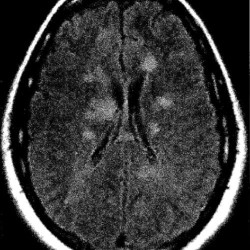

- MRI imaging with contrast is the most important imaging modality in the workup of possible MS.

- Demyelinating lesions related to MS are ovoid, >3 mm in diameter, and are typically located in particular regions: periventricular (Dawson’s fingers), juxtacortical, cortical, or spinal cord.